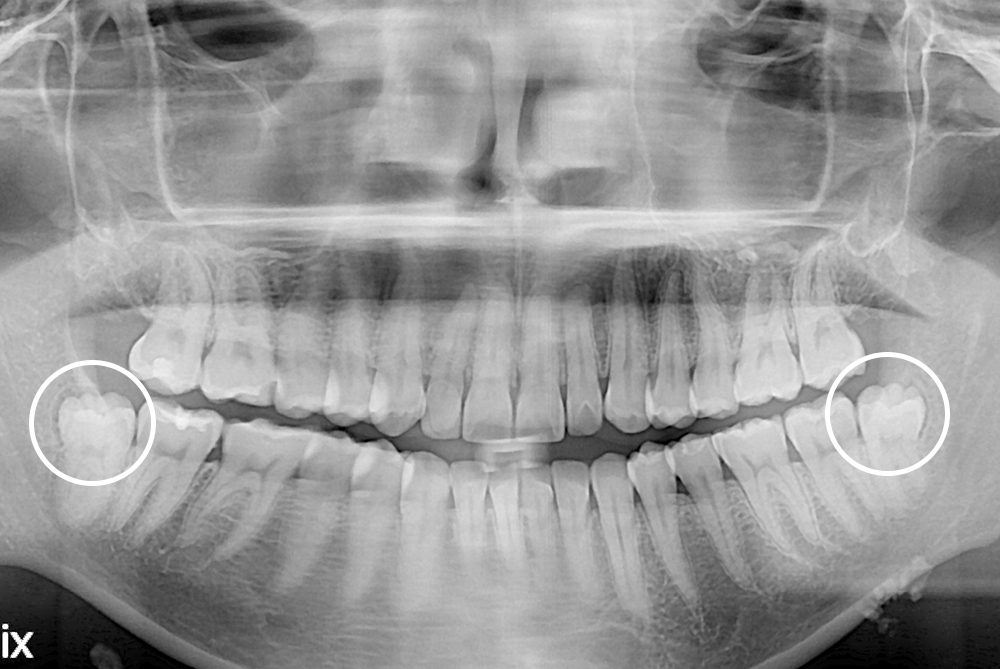

[사랑니] 매복 사랑니 발치

치료후 : 2021-12-31

세종치과는 구강악안면외과학 박사이신 원장님이 발치하는 치과입니다.